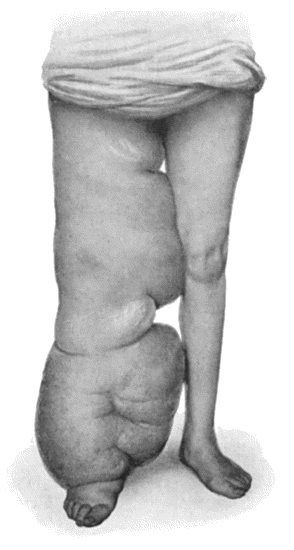

135.Cadaver, illustrating the alterations in the Lower Limbs resulting from Ostitis Deformans 475

140.Multiple Cartilaginous Exostoses 484